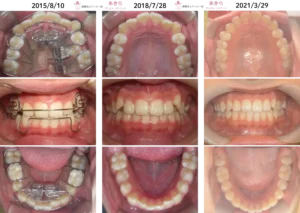

過蓋咬合 症例 嚙み合わせが深く前歯が見えないケース

症例写真

2022年4月28日⇒2024年10月7日(2022年5月プレオルソスタート)

2022年4月28日⇒2024年10月7日